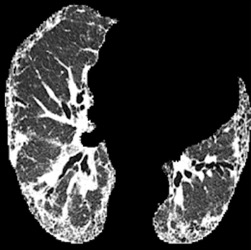

In the field of medical imaging, particularly in tasks related to early disease detection and prognosis, understanding the reasoning behind AI model predictions is imperative for assessing their reliability. Conventional explanation methods encounter challenges in identifying decisive features in medical image classifications, especially when discriminative features are subtle or not immediately evident. To address this limitation, we propose an agent model capable of generating counterfactual images that prompt different decisions when plugged into a black box model. By employing this agent model, we can uncover influential image patterns that impact the black model's final predictions. Through our methodology, we efficiently identify features that influence decisions of the deep black box. We validated our approach in the rigorous domain of medical prognosis tasks, showcasing its efficacy and potential to enhance the reliability of deep learning models in medical image classification compared to existing interpretation methods. The code will be publicly available at https://github.com/ayanglab/DiffExplainer.